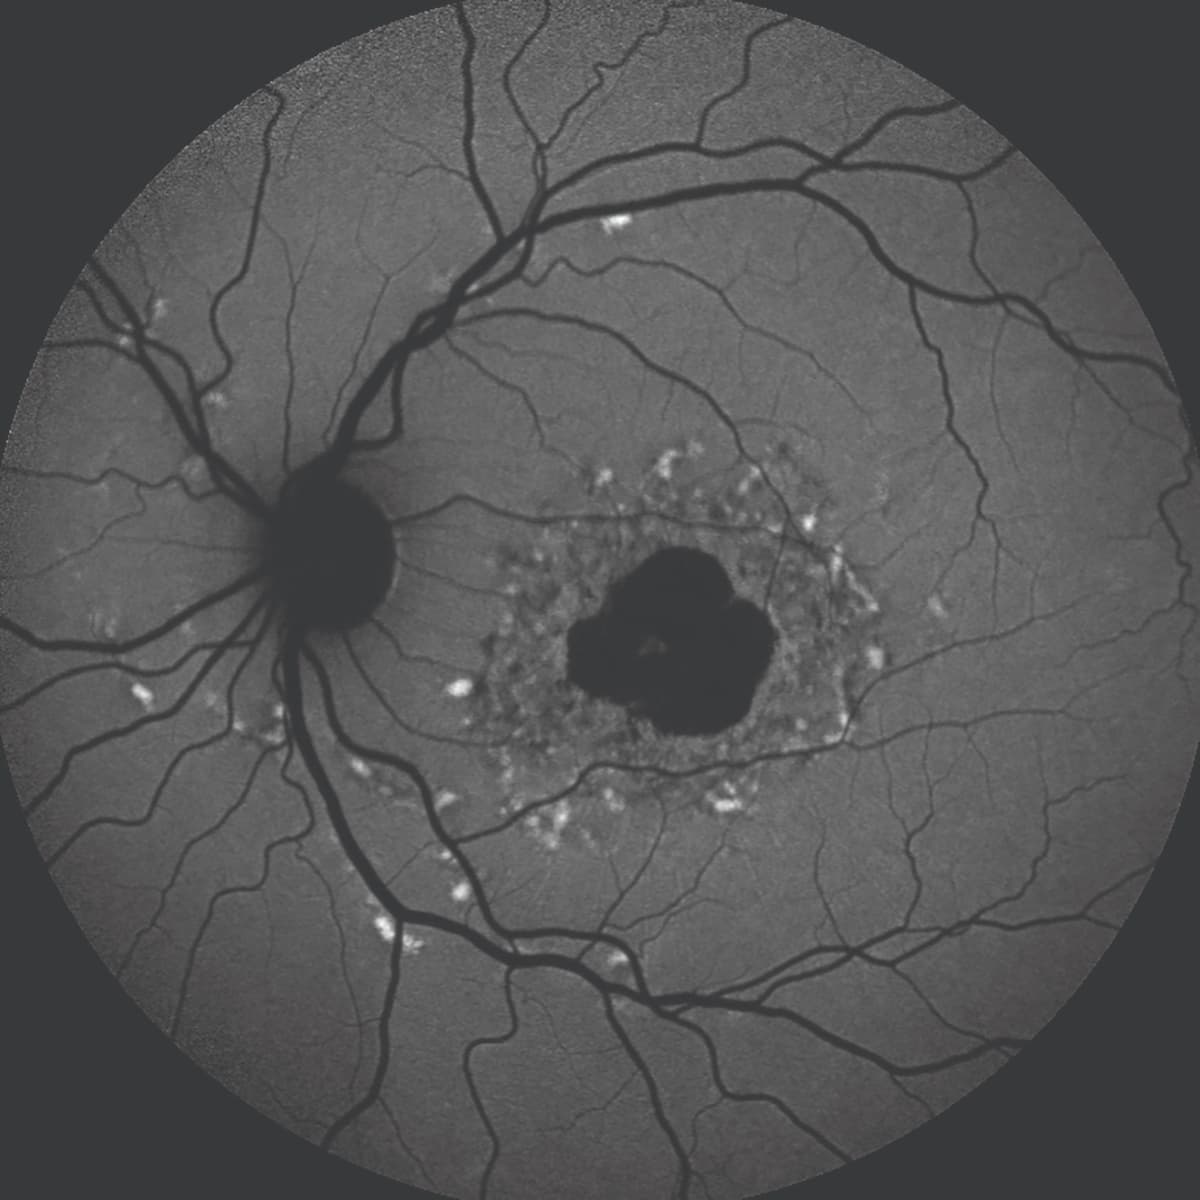

Fundus autofluorescence (FAF) allows visualization of the typical hallmark hyperautofluorescence pattern along the border of a GA lesion. The technique uses the natural fluorescence of lipofuscin in the retinal pigment epithelium (RPE) and can also help in differentiating IRDs, particularly by identifying RPE changes and atrophy (Figure 1).

Figure 1 (top): A blue fundus autofluorescence image of the left eye of a woman aged 86 years with a multifocal pattern of geographic atrophy with perilesional hyperautofluorescence.